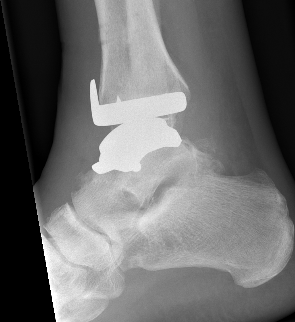

Infinity implant STAR implant Inbone

Agility Salto Tolaris Trabecular metal

3rd generation implants

- minimal bony resection with uncemented implants

- talus resurfacing with smooth surface

- +/- stems or pegs

- highly crosslinked polyethelene implant - mobile bearing versus fixed bearing